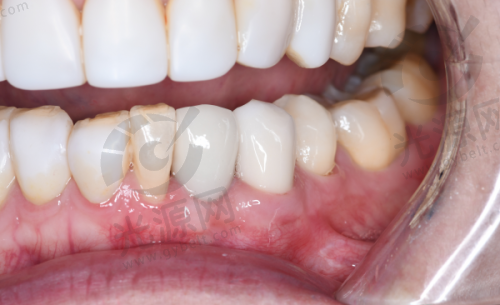

唐山地区的种植牙技术近年来不断更新,尤其是数字化种植技术和微创种植技术逐渐开始普及。这能有效降低患者的手术风险和修复时间,提高成功几率。

实例1:患者李女士在唐山协和口腔医院做了种植牙,选用的是韩国登腾种植体,手术十分顺利,术后也没有明显的肿胀,李女士表示非常满意,咀嚼能力明显提升。